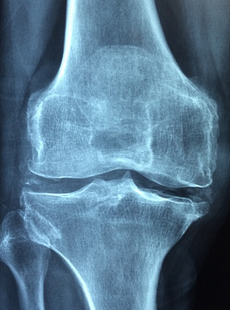

1. 퇴행성 관절염 (골관절염): 이는 뼈끝을 감싼 연골이 닳아 발생하며 통증과 부종을 일으키는 질환입니다. 노화, 관절에 생기는 상처나 감염 등이 원인이 되어 발생합니다 .

수술 요법은 약물 요법이나 물리 요법으로 증상이 호전되지 않거나 관절의 손상이 심한 경우에 시행하는 방법입니다. 수술 요법에는 관절내 주사요법과 인공관절 수술이 있습니다. 관절내 주사요법은 코르티코스테로이드나 히알루론산 등의 약물을 직접 관절 내부에 주입하는 방법으로, 염증과 통증을 잠시 완화시켜줍니다. 인공관절 수술은 손상된 관절을 인공적인 재료로 교체하는 방법으로, 통증을 없애고 관절의 기능을 회복시켜줍니다.